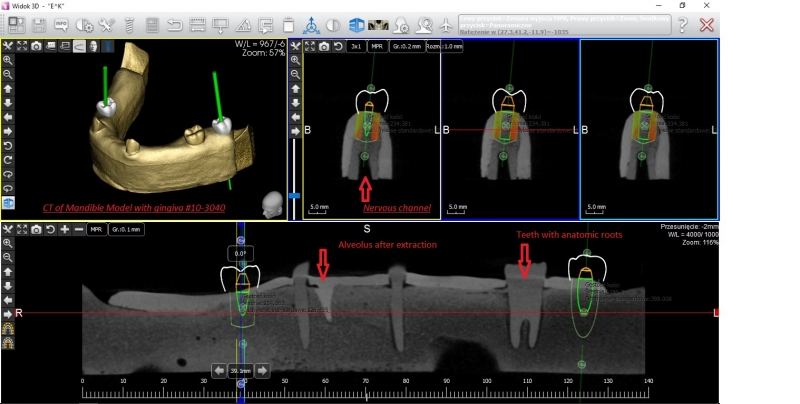

Żuchwa do fantomów z wyrostkiem zębodołowym wyścielonym imitacją błony śluzowej oraz zębami 10-3040

• Żuchwa do fantomów z wyrostkiem zębodołowym wyścielonym imitacją błony śluzowej oraz zębami 10-3040

Żuchwa do fantomów z wyrostkiem zębodołowym wyścielonym imitacją błony śluzowej oraz zębami wraz z ich korzeniami  w pozycji 37, 33, 43 oraz z niezagojonym zębodołem w pozycji 42. W modelu odwzorowano kanały żuchwy i otwory bródkowe. Płytka mocująca umożliwia montaż do większości fantomów znajdujących się na rynku. Model ten można zamontować w dowolnym artykulatorze lub fantomie dentystycznym popularnym na rynku (zalecany manekin to 11-1000).

Poniżej znajduje się przycisk umożliwiający ściągnięcie pliku STL przeznaczonego do wykonanie szablonu do szkoleń implantacyjnych z użyciem modelu.

Numer katalogowy 10-3040